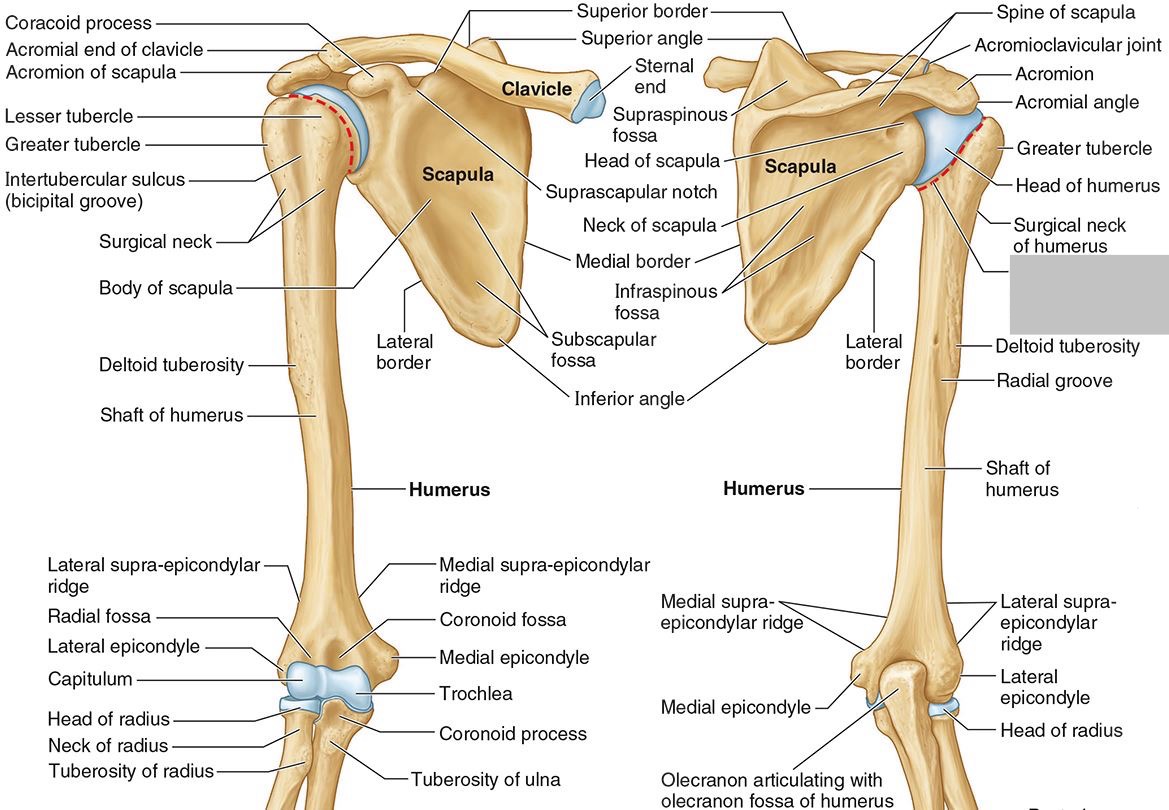

What is the only bone in the upper arm?

The humerus

What part of the humerus is this?

The head of the humerus articulates with the scapula at the glenohumeral joint.

What part of the humerus is this?

The anatomic neck is an indentation distal to the head and provides an attachment for the fibrous joint capsule of the glenohumeral joint.

What part of the humerus is this?

The greater tubercle lies lateral and distal to the anatomic neck.

What part of the humerus is this?

The lesser tubercle lies on the anterior/medial side of the humerus, just distal the anatomic neck.

What part of the humerus is this?

The intertubercular (bicipital) groove lies between the greater and lesser tubercles.

What part of the humerus is this?

The surgical neck is a narrow area distal to the tubercles. It is a common site for proximal humerus fractures.

What part of the humerus is this?

The humeral shaft features the deltoid tuberosity laterally for the distal insertion of the deltoid muscle.

What part of the humerus is this?

The radial groove is an oblique depression that contains the radial nerve and deep brachial artery.

Which parts of the humerus is this?

The medial and lateral epicondyles are distal prominences to which many forearm tendons attach, near the elbow joint.

Which parts of the humerus is this?

The medial and lateral supracondylar ridges extend superiorly from the medial and lateral epicondyles.

Which parts of the humerus is this?

The trochlea and the capitulum (the condyles) are the most distal surfaces of the humerus, where it articulates with the forearm bones at the elbow joint

What part of the humerus is this?

The olecranon fossa is a posterior depression above the trochlea that receives that olecranon process of the ulna

What part of the humerus is this?

The coronoid fossa is an anterior depression above the trochlea that receives that coronoid process of the ulna.